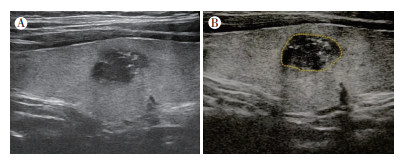

1.3 AI辅助诊断软件采用什维新智医疗科技(上海)有限公司的超声影像智能辅助诊断系统,将能清晰显示甲状腺结节声像图特征的图像导入超声AI辅诊系统,手动勾画感兴趣区(region of interest, ROI),将结节边界全部圈定在内,软件自动分析结节回声、边缘和钙化等特征的情况,同时得出C-TIRADS分类结果,当所得结果不一致时取分类最高者(图 1)。

| 注 A:右侧腺叶结节,位于中部,大小1.29 cm×0.84 cm,实性低回声,边缘不光整,内见点状强回声,C-TIRADS 4C类;B:AI辅助诊断系统自动勾画甲状腺结节(纵切面),C-TIRADS 4C类 图 1 医师和AI辅助诊断系统依据C-TIRADS对1例32岁女性患者的甲状腺结节分类 Fig.1 Thyroid nodules in a 32-year-old female patient classified by physicians and the AI-assisted diagnosis system based on C-TIRADS |